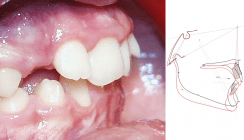

Wie die Abbildung 1 zeigt, treten unter  Verwendung lingualer Apparaturen schon bei geringsten Torqueabweichungen erhebliche vertikale Zahnstellungsprobleme auf. Als Konsequenz ergibt sich eine deutlich höhere Anforderung an die linguale Apparatur, was die Kontrolle der dritten Ordnung betrifft. Um durch einen falschen Torque induzierte vertikale Abweichungen weitestgehend zu vermeiden, sollte die eingesetzte Bracket-Bogen-Kombination die Torqueabweichungen bis auf wenige Grad herunterkorrigieren: Bei flachen lingualen Apparaturen auf unter 3 Grad, bei lingualen Apparaturen mit größerem Bogen-Zahn-Abstand (dickere Lingualbrackets, Bracketpositionierung nach einer sogenannten „Straight Wire“-Philosophie) möglichst auf mindestens 1 Grad. Dieses Ziel ist sicherlich mit einem untermaßigen 17,5 x 17,5  TMA-Bogen vom Prinzip her schon nicht zu erreichen. Dabei ist neben der Bogendimension auch und in erster Linie die Bracketslotdimension von entscheidender Bedeutung.